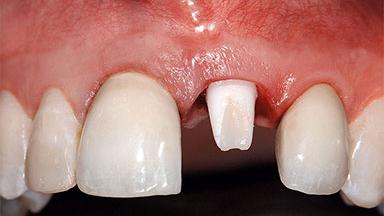

Replacement of a Missing Upper Left Central Incisor: Late Placement of an RC Bone Level Implant, CAD/CAM Zirconia Abutment

A healthy 37-year-old female patient was referred for a consultation on the replacement of missing tooth 21 with an implant-supported restoration. She stated that several years previously the tooth had been traumatically avulsed following a motor vehicle accident. The tooth was replaced with a three-unit fixed partial denture (FPD) immediately afterwards. Over time, she became disillusioned with the FPD and looked for a different option, including orthodontic therapy. She presented still in her orthodontic appliances, with the pontic sectioned free from the FPD but attached to the archwire. Her orthodontist felt that orthodontic treatment had been successfully completed, but nevertheless referred her before removing the appliances in case adjustments were necessary.

Mesio-Distal Space Symmetry +/- 1 mm of contra-lateral tooth